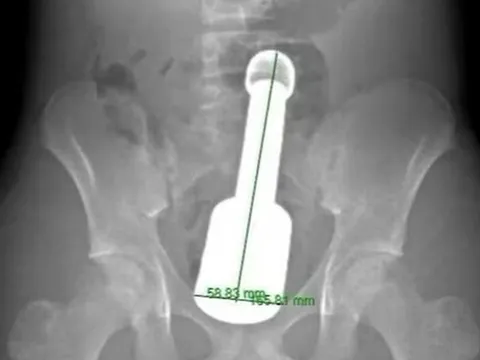

Bác sĩ cảnh báo một tai nạn nguy hiểm dễ gặp ở người già

(NLĐO)- Người cao tuổi, người mắt kém, uống nhiều thuốc cùng lúc dễ nhầm lẫn nuốt cả vỏ thuốc nên cần có người nhà để ý hỗ trợ.